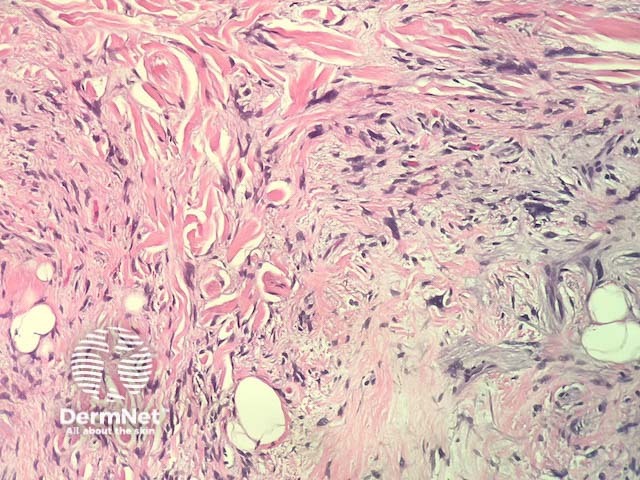

In neurofollicular hamartoma, the histopathology shows a nodular dermal spindle cell proliferation surrounded by prominent sebaceous glands. The spindle cells are plump or wavy. The sebaceous proliferation surrounds the mesenchymal component (figures 1–3).

Figure 2